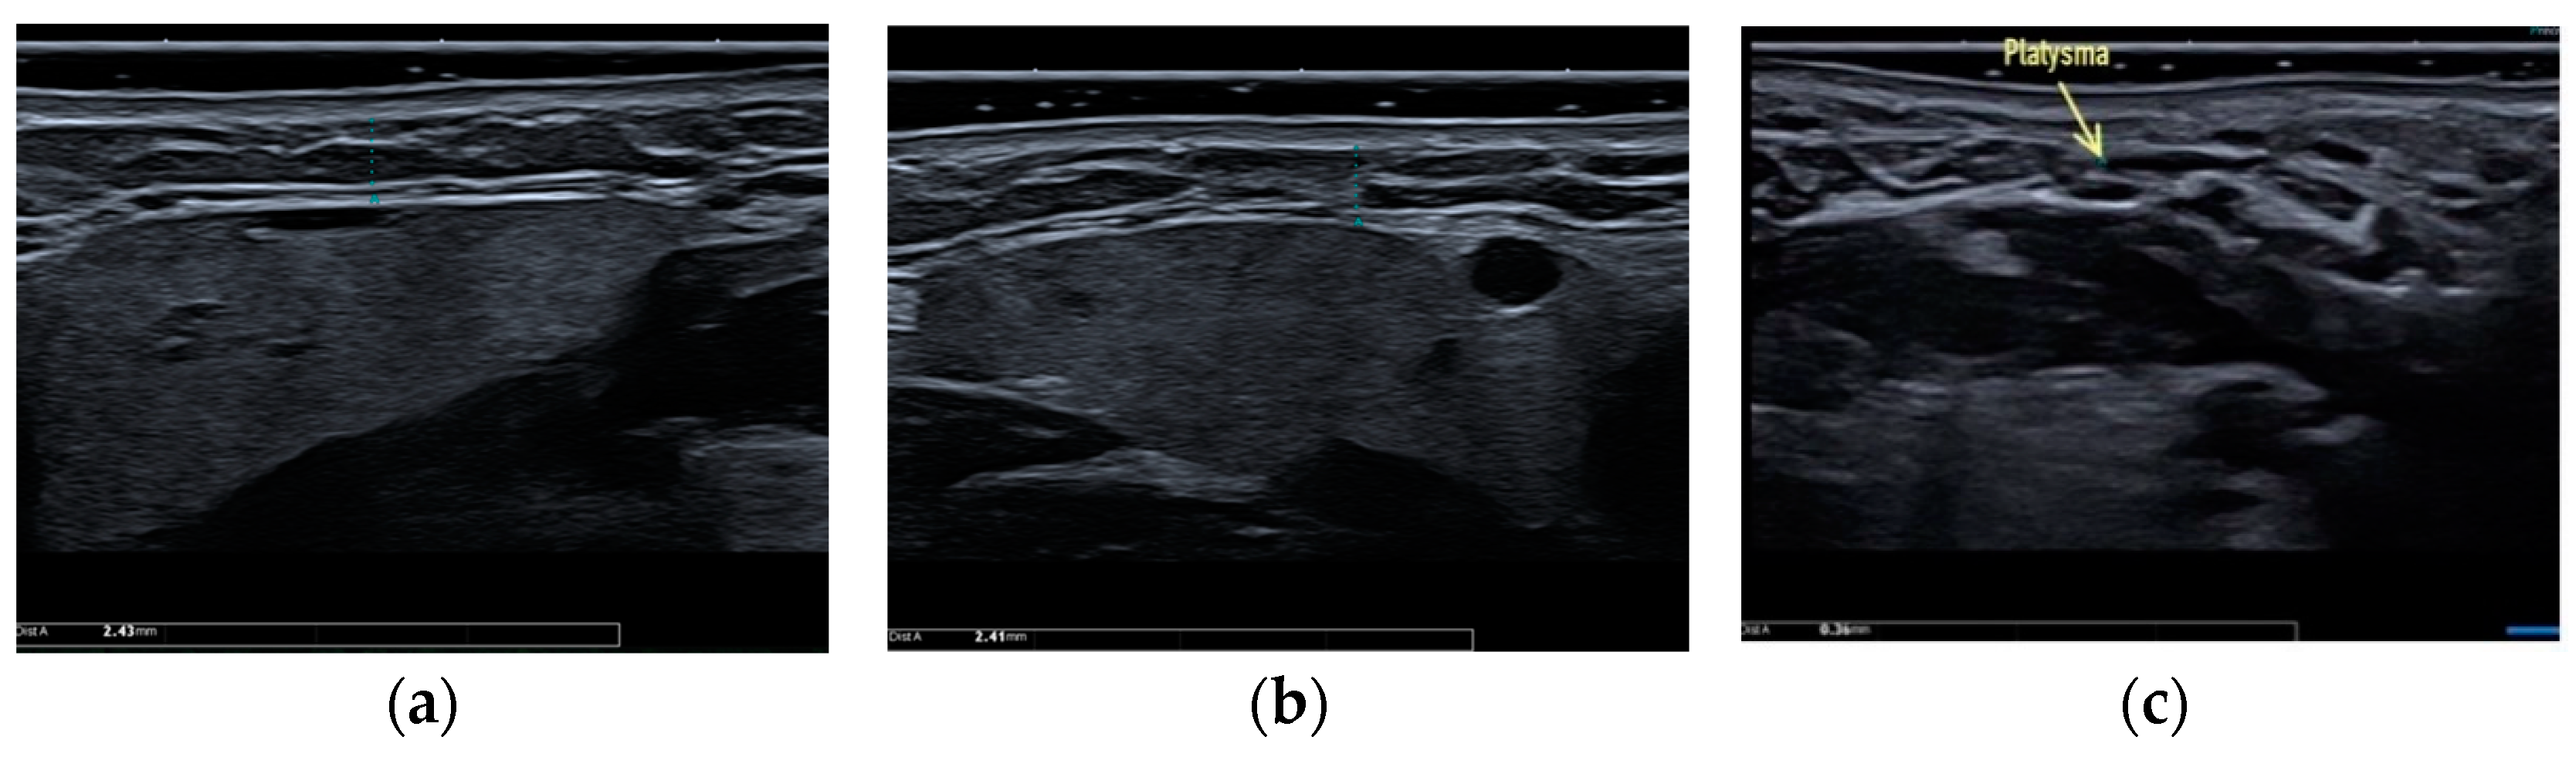

- Sharobaro, V.; Alimova, S.; Telnova, A.; Shamanaeva, L. Ultrasound diagnosis of age-related involutional changes in the lower third of face and neck to determine treatment techniques. Pak. J. Med. Sci. 2021, 37, 272–276. [Google Scholar] [CrossRef]

- Alimova, S.M.; Sharobaro, V.I.; Telnova, A.V.; Stepanyan, E.E. Planning of methods of surgical correction of soft tissues of the face and neck. Med. Vis. 2021, 25, 47–52. [Google Scholar] [CrossRef]

- Mashkevich, G.; Wang, J.; Rawnsley, J.; Keller, G.S. The Utility of Ultrasound in the Evaluation of Submental Fullness in Aging Necks. Arch. Facial Plast. Surg. 2009, 11, 240–245. [Google Scholar] [CrossRef]